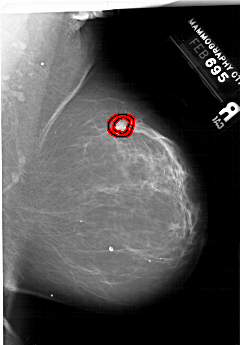

A_1999_1.RIGHT_CC

RIGHT_CC LINES 6871 PIXELS_PER_LINE 4336 BITS_PER_PIXEL 12 RESOLUTION 43.5 OVERLAY

FILE: A_1999_1.RIGHT_CC.OVERLAY

TOTAL_ABNORMALITIES 1

ABNORMALITY 1

LESION_TYPE MASS SHAPE IRREGULAR MARGINS SPICULATED

ASSESSMENT 5

SUBTLETY 3

PATHOLOGY MALIGNANT

TOTAL_OUTLINES 2

BOUNDARY

CORE